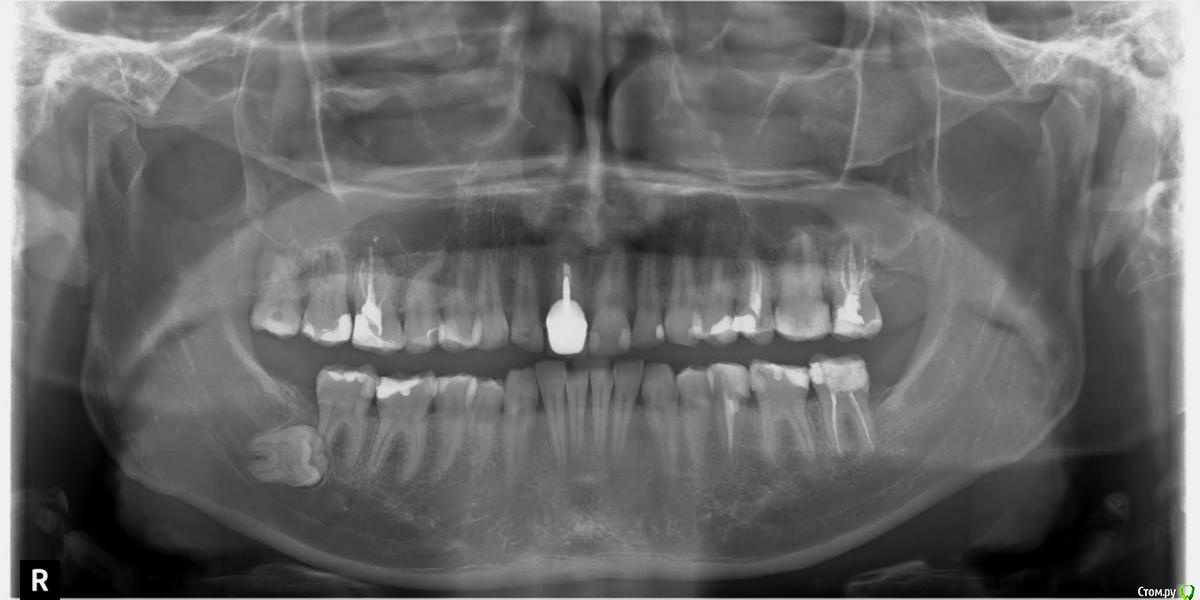

timson Опубликовано 18 марта, 2017 Поделиться Опубликовано 18 марта, 2017 (изменено) Здравствуйте, помогите советом пожалуйста. Ситуация сследующая: Почувствовал чувство давления справа вверху и внизу, врач терапевт осмотрел полость рта и пульпит не нашел.Направлен я был на ортопантомограмму https://yadi.sk/i/6HkZCRSm3FEaGc, на ней обнаружена ретенция 8 зуба мудрости справа.Обратился к стоматологу хирургу , у него сделана фрагментарная КТ правой стороны челюсти. https://yadi.sk/d/FdOB70aA3ErpHn -образ ктhttps://yadi.sk/d/cf0GB6vR3ErpHt программа в архиве deamons tools в rar архивеКто не знает, устанавливаем программу daemons tools, выбираем монтировать и указываем скаченный образ.В итоге обнаружена радиальная киста 6 зуба спрва вверху, из за предположительной причины, некачественная эндодонтия, не закрыты каналы.(Обратился в ЧЛХ отделение, где 6 зуб хотят удалить.После чего обратился в частную клинику, где врач стоматолог хирург позвонив в ЧЛХ отделение, посоветовавшись там с доктором, отказался заниматься этим зубом.За ретенированный зуб берется, просит 7000.Обратился по совету врача хирурга к опытному хирургу. Его заключение надо заняться 6 зубом и кистой-цена вопроса 5000, а для удаления ретинированного зуба рекомендовал депульпировать вначале 7 зуб, что бы избежать затем осложнений и сохранить 7 зуб. Хотелось бы сохранить зуб,не очень понятно почему нельзя удалить корни зубов и не удаляя зуб.Помогите кто может сталкивался с такой проблемой.Клиники гайморита пока слава Богу нет. Отмечается эпизодическое чувство давления снизу справа.Хотелось бы сохранить зуб, можно ли в данном случае сохранить зуб и какие варианты кто предложит.Так же интересует стоит ли идти на амбулаторное иссечение кисты или стационар ЧЛХ? Спасибо за внимание. Изменено 18 марта, 2017 пользователем timson Ссылка на комментарий